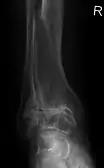

Lateral X-ray scan of ankle with secondary osteoarthritis

Lateral

Frontal X-ray scan of ankle with secondary osteoarthritis

Frontal

Secondary osteoarthritis of the ankle (due to an old bone fracture) in an 82-year-old woman